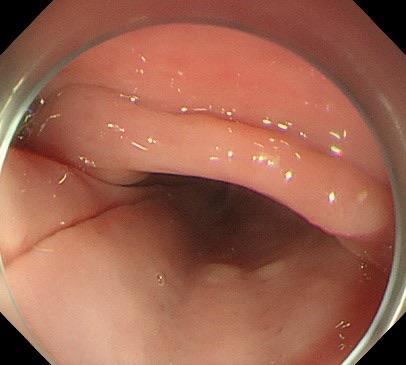

赵奶奶听了钟教授的病情解释后,恳请钟教授尽快手术。钟教授当天就安排赵奶奶住院检查,行术前评估,次日就给赵奶奶完成了内镜下微创手术:隧道内镜下食管憩室嵴切开术。钟教授运用内镜电刀在食管憩室上方建立“隧道”入口,打通“隧道”,在“隧道”内暴露出憩室嵴,最后应用内镜刀切开憩室嵴肌肉,在食管腔观察憩室嵴消失,金属夹关闭“隧道”入口。手术顺利,整个手术过程仅仅用时30分钟。术后复查造影,造影剂流出食管顺畅,不再潴留于食管憩室。赵奶奶术后经过禁食、胃肠减压、抑酸、营养支持等治疗,1天后进食流质饮食无明显不适,未再呕吐。术后逐步增加饮食,赵奶奶也未再呕吐,并且体重逐步增加,精神越来越好。就这样,困扰了赵奶奶好多年的呕吐,竟然这么快就治好了。

图1  食管巨大憩室,术前憩室嵴明显,造影剂滞留食管憩室